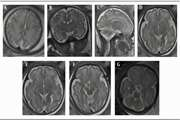

Correlation of semi quantitative findings of endolymphatic hydrops in MRI with the audiometric findings in patients with Meniere’s disease Jul 21 2024 - 09:02